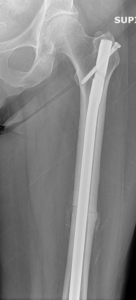

Nonunion and malunion repair related to post-traumatic conditions and/or prior surgery

Acute fracture care of the pelvis and the extremities